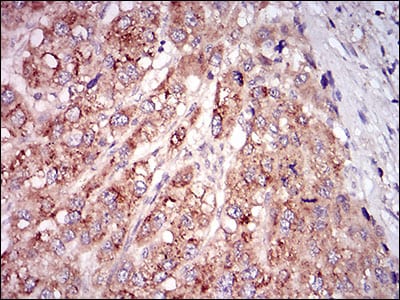

分类: 科研抗体货号: 30622别名: GDF8; MSLHP应用: IHC反应种属: Human